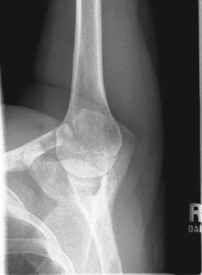

Tangential projection—intertubercular (bicipital) groove (Fisk modification) (S)

Tangential projection intertubercular groove critique